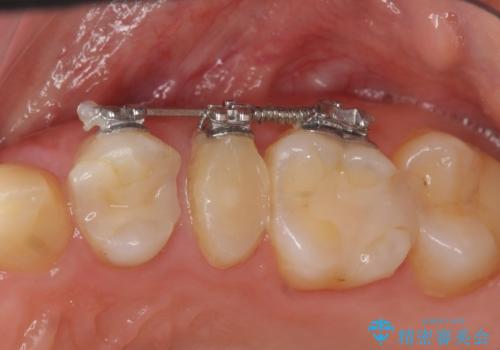

- 部分ワイヤー矯正

- 50.6万円(ジルコニアクラウン×3・仮歯×3・部分矯正)費用は治療当時の料金となります

当初、歯ぐきよりも深い虫歯の存在や、歯のポジションに問題がありましたがマルチブラケットを用いた部分矯正で行うことで歯の挺出同時に適切な位置へと歯を移動させ、歯周環境を整えたセラミック治療を行うことができました。